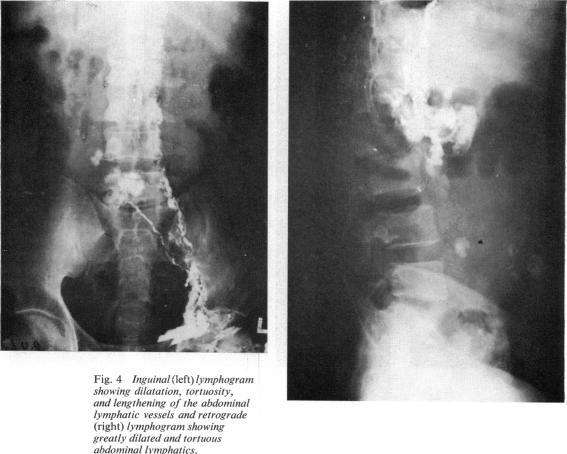

The changes in the thoracic duct were studied in schistosomatic hepatic fibrosis, particularly in cases with ascites. The postmortem findings, lymphangiography, and clinical thoracic duct cannulation showed that, particularly in cases with ascites, the thoracic duct is dilated, pressure within is raised, and the lymph flow is increased. The significance of these findings is discussed in relation to the site and the treatment of ascites.